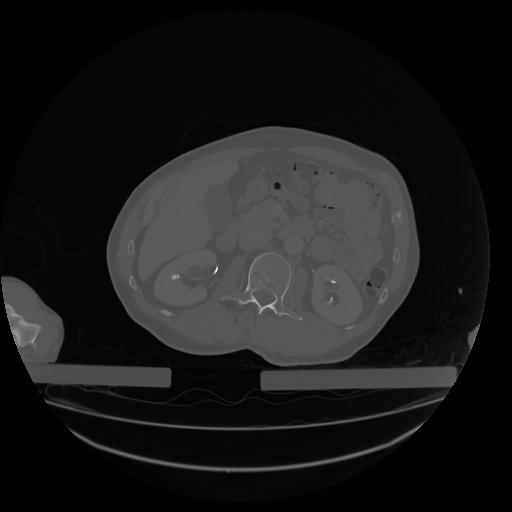

34 CUERPO,CE,Vol,1.0,CUERPO,,